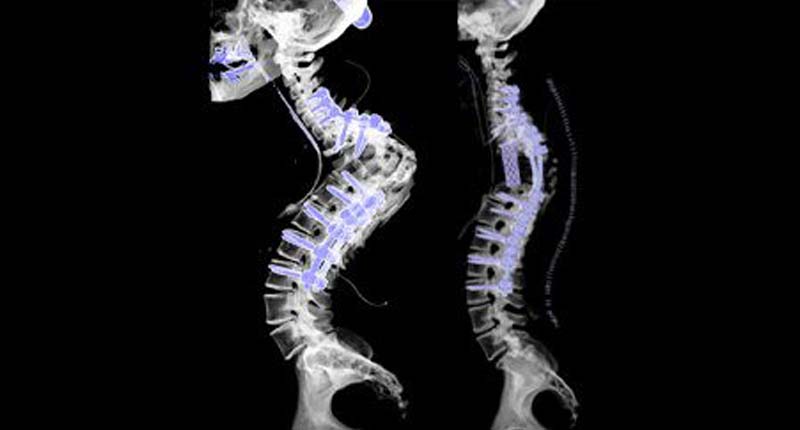

Spinal Reconstruction compromises of more than one level of spine & helps correct significant spinal deformations, supports a new shaped spine with the aid of rods and pins, and combines the vertebrae.If an entire vertebrae segment is diseased, then the complete vertebrae is removed and replaced with an artificial device.

Depending on the severity of spine deformity, spine surgeons use a variety of surgical techniques during spinal reconstruction surgery, like Minimally invasive surgery, artificial disc replacement, stereotactic spine radiosurgery, spinal fusion, and other operational methods may be performed.

A majority of the time, spine reconstruction involves spinal fusion surgical procedures. The spinal fusion procedure consists of removing the disc between two affected vertebrates & binding the vertebrae together. Fusing vertebrae eliminates the motion and lessen the pain.